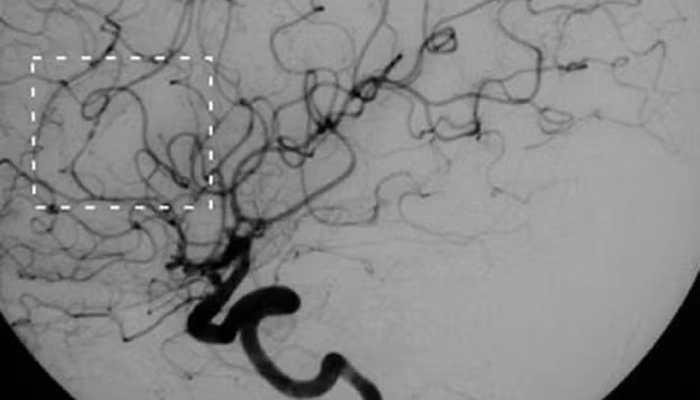

Chụp mạch (angiography): đánh giá chi tiết hệ mạch tổn thương

Hình ảnh chụp mạch máu não cho thấy viêm mạch não, với các mạch máu có hình dạng hạt hoặc ngoằn ngoèo bất thường